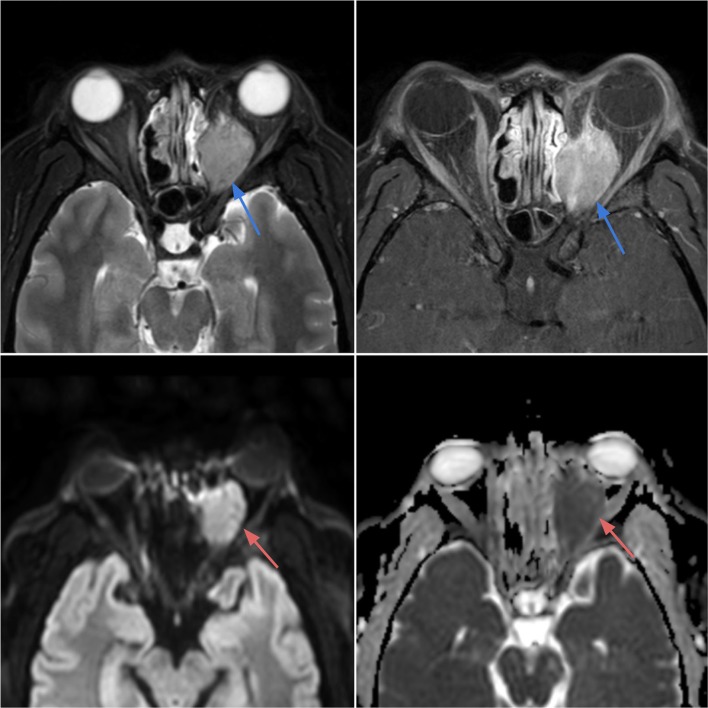

Case 5.

Rhabdomyosarcoma of the left orbit in a 28-year-old female with blurry vision, proptosis and orbital pain with movement. Axial T2-weighted (top left) and T1 post-contrast (top right) images demonstrate a T2 heterogeneously hyperintense mass with avid enhancement within the left posterior orbit (blue arrows), with extraconal components eroding the medial orbital wall and extending into the nasal cavity. The mass exhibits bright signal on DWI (bottom left) and dark signal on ADC (bottom right) reflecting low diffusivity in keeping with the highly cellular tumor (red arrows)